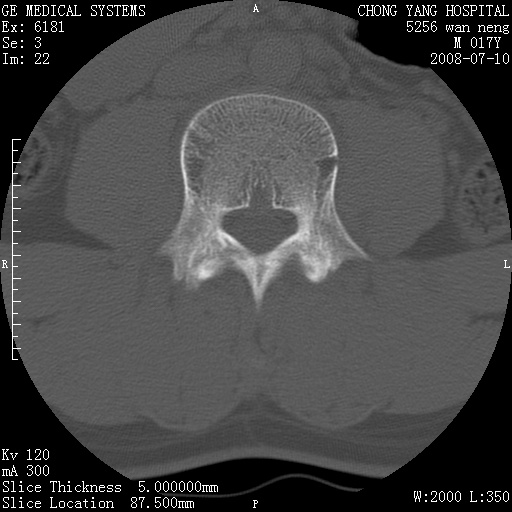

腰3、4椎弓崩裂

腰3、4椎弓不连

支持:腰3、4椎弓峡部崩裂。

腰3、4椎弓峡部不连

支持:腰3、4椎弓峡部崩解。

腰3、4,如受过外伤则为陈旧骨折,否则为骨质不连

图片漂亮,目前也只能看到腰3、4骨质不连

腰3、4椎弓峡部裂。

腰3、4椎弓峡部裂。支持

重建图像见多个椎弓峡部不连(不足为据),平扫未见异常。

支持腰3、4椎弓峡部崩裂。